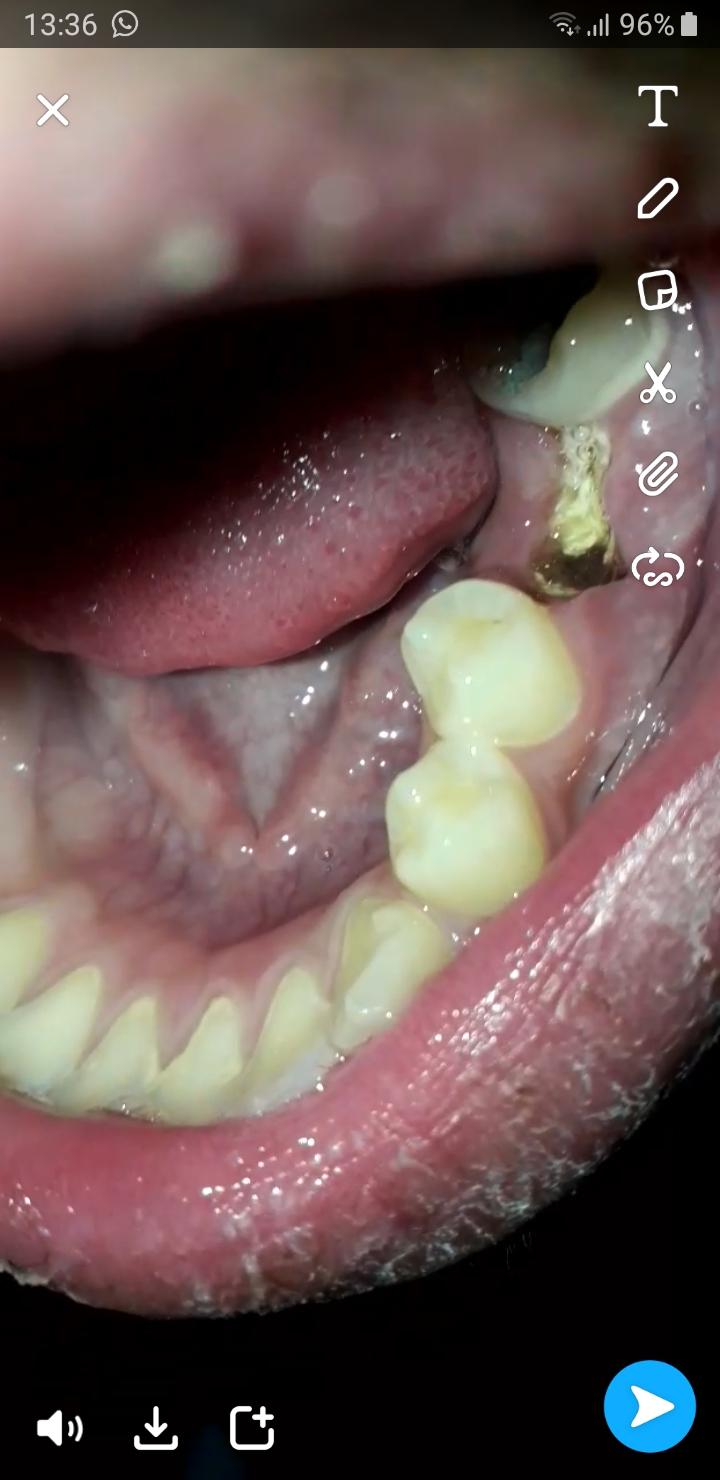

Zahn Gezogen Was Ist Des Entzundet

Zahn Gezogen Ist Die Wunde Entzundet Gesundheit Zahnarzt Entzundung